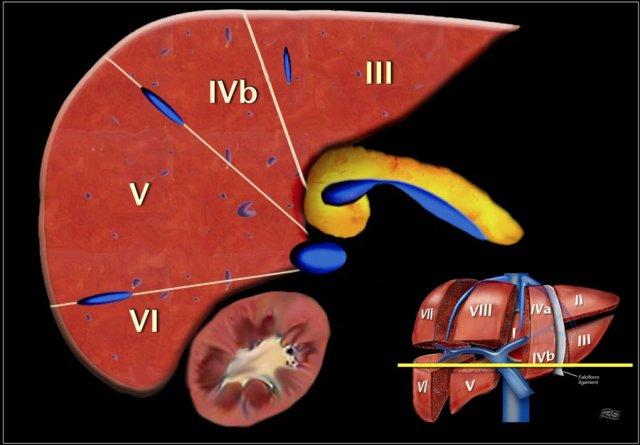

Đây là một hình minh họa khác về giải phẫu phân thùy chức năng của gan.

Tĩnh mạch cửa

Tĩnh mạch cửa chia gan thành các phân thùy trên và dưới.

Tĩnh mạch cửa trái và phải phân nhánh lên trên và xuống dưới để đi vào trung tâm của mỗi phân thùy.

Couinaud chia gan thành gan trái và gan phải về mặt chức năng bởi một khe cửa chính chứa tĩnh mạch gan giữa.

Đường này được gọi là đường Cantlie.

Đường Cantlie chạy từ giữa hố túi mật ở phía trước đến tĩnh mạch chủ dưới ở phía sau.